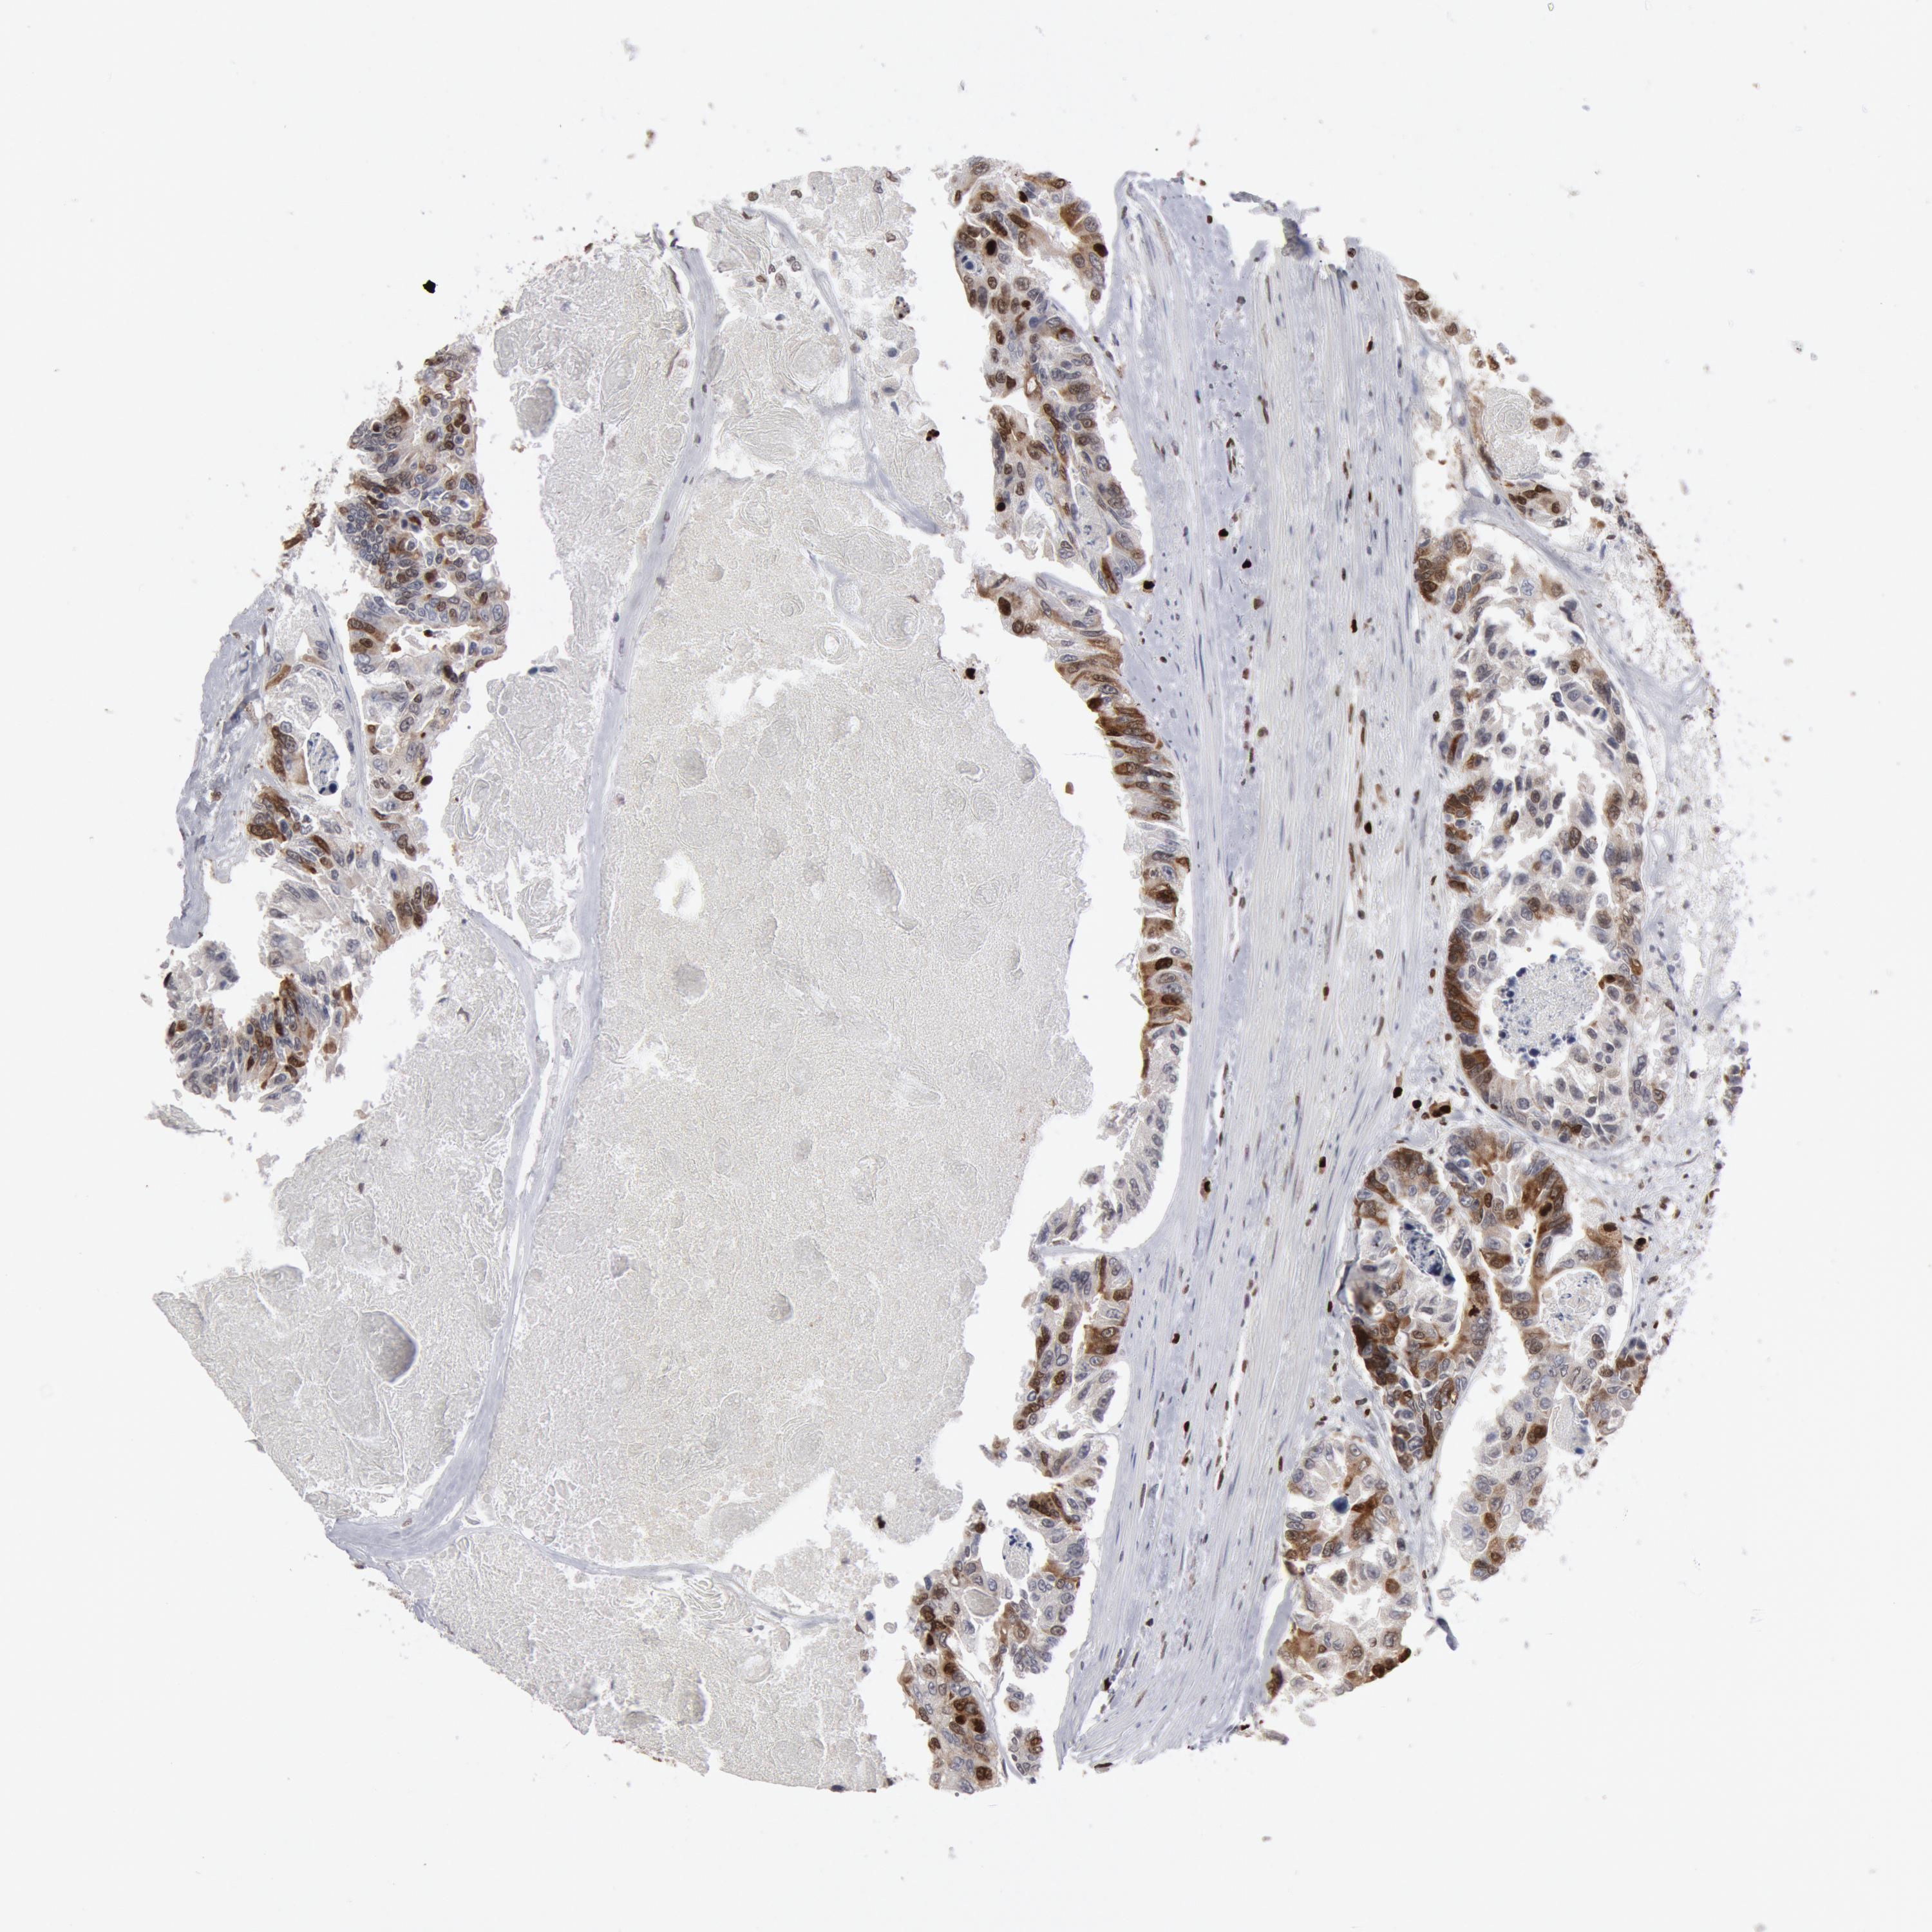

CANCER COLORECTAL CANCER Show tissue menu

ANTIBODIES

AND

VALIDATION